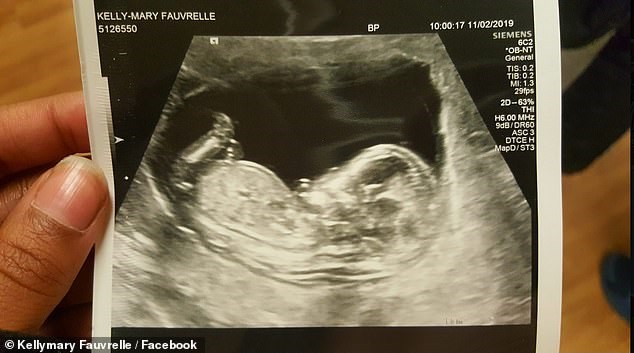

Σε μία δεύτερη σύλληψη προχώρησε η βρετανική αστυνομία σχετικά με τον θανάσιμο τραυματισμό με μαχαίρι της 26χρονης εγκύου Κέλι Μέρι Φοβρέλ στο νότιο Λονδίνο.

Η αστυνομία εκλήθη σε μια διεύθυνση στις 03:30 τα ξημερώματα Παρασκευής προς Σάββατο, όταν βρήκε την 26χρονη γυναίκα τραυματισμένη. Γέννησε στο σημείο με τη βοήθεια διασωστών και μεταφέρθηκε νεκρή στο νοσοκομείο. Το βρέφος νοσηλεύεται σε κρίσιμη κατάσταση.Η αστυνομία συνέλαβε έναν 37χρονο που τώρα αφέθηκε ελεύθερος αλλά παραμένει υπό έρευνα. Παράλληλα, συνελήφθη ένας 29χρονος και οδηγήθηκε σε αστυνομικό τμήμα στο νότιο Λονδίνο όπου παραμένει για ανάκριση.